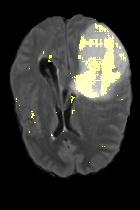

Current unsupervised anomaly localization approaches rely on generative models to learn the distribution of normal images, which is later used to identify potential anomalous regions derived from errors on the reconstructed images. However, a main limitation of nearly all prior literature is the need of employing anomalous images to set a class-specific threshold to locate the anomalies. This limits their usability in realistic scenarios, where only normal data is typically accessible. Despite this major drawback, only a handful of works have addressed this limitation, by integrating supervision on attention maps during training. In this work, we propose a novel formulation that does not require accessing images with abnormalities to define the threshold. Furthermore, and in contrast to very recent work, the proposed constraint is formulated in a more principled manner, leveraging well-known knowledge in constrained optimization. In particular, the equality constraint on the attention maps in prior work is replaced by an inequality constraint, which allows more flexibility. In addition, to address the limitations of penalty-based functions we employ an extension of the popular log-barrier methods to handle the constraint. Comprehensive experiments on the popular BRATS'19 dataset demonstrate that the proposed approach substantially outperforms relevant literature, establishing new state-of-the-art results for unsupervised lesion segmentation.